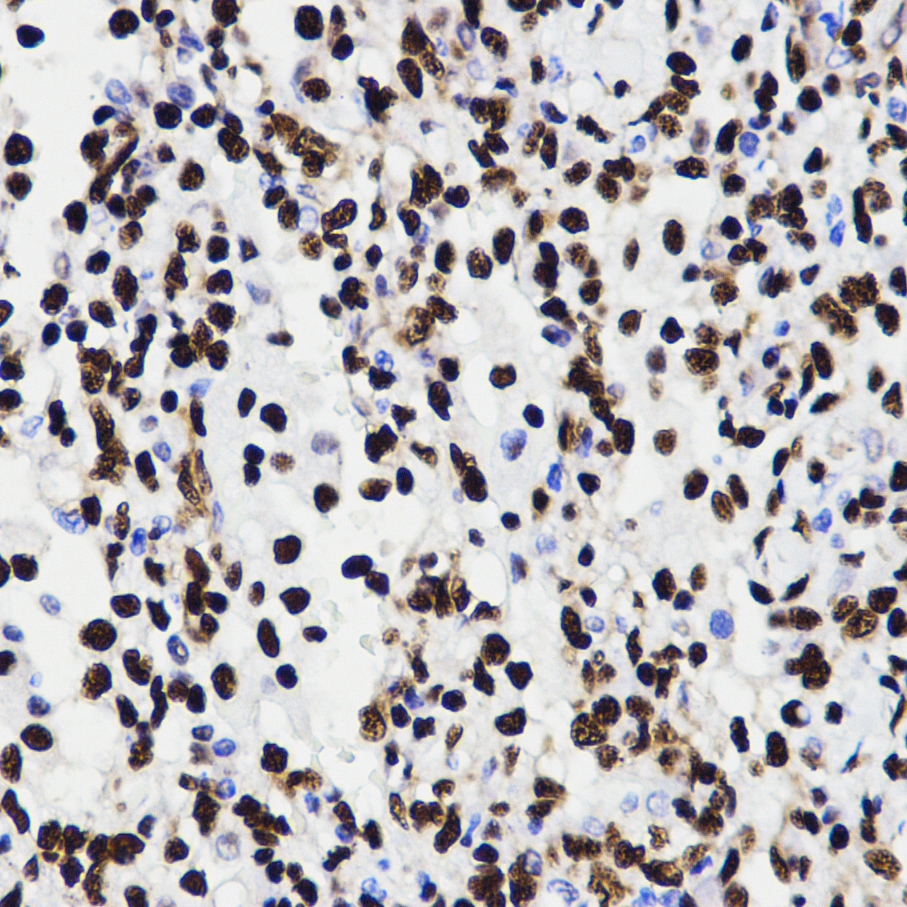

• A2553: image 3

Immunofluorescence analysis using HMGB1 antibody.